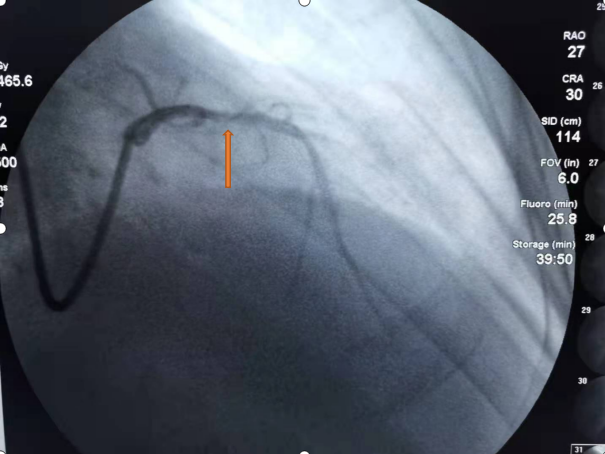

经过近一小时的紧张手术后,成功对病变处予以精确处理。术后复查IVUS,提示实际测得有效官腔直径2.7mm,钙化环已打开、有效血流面积4.0mm²,取得了非常好的治疗效果。术后患者安全返回病房,生命体征平稳,症状明显缓解,患者及家属对手术治疗效果非常满意。

术后1

术后2